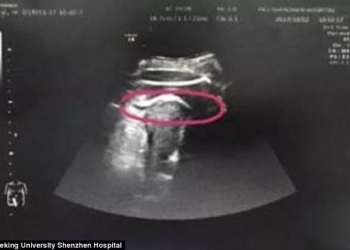

Queria nascer: bebê perfura o útero da mãe com chutes

Uma mulher, de 25 anos, identificada apenas como Sra. Zhang, passou por uma situação difícil na China com o desenrolar...